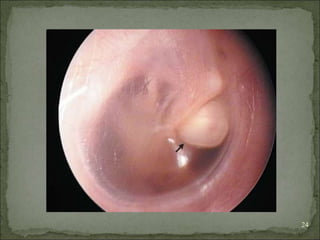

CONGENITAL

 Embroyonic epidermal cell rests in the middle ear cleft/

temporal bone

 Middle ear, petrous apex,cerebellopontine angle

 Middle ear: white mass behind an intact tympanic

membrane -> conductive hearing loss

 Discovered: routine exam/myringotomy

 May spontaneously rupture- TM -> discharging ear